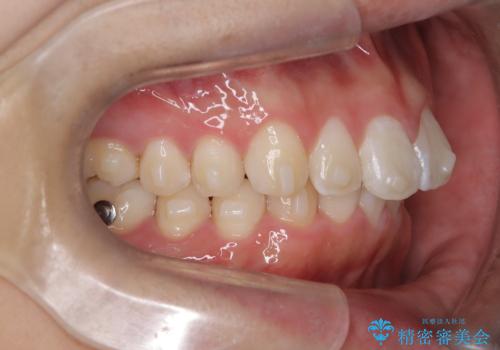

- 歯のデコボコと過蓋咬合を主訴に来院された患者様です。

アーチの拡大とIPRを行い非抜歯で治療を行いました。

歯を抜かずに叢生(デコボコ歯列)と過蓋咬合を改善する事が出来ました。

インビザラインによる治療でも十分に美しい歯並びを実現でき、患者様にも大変ご満足いただけました。